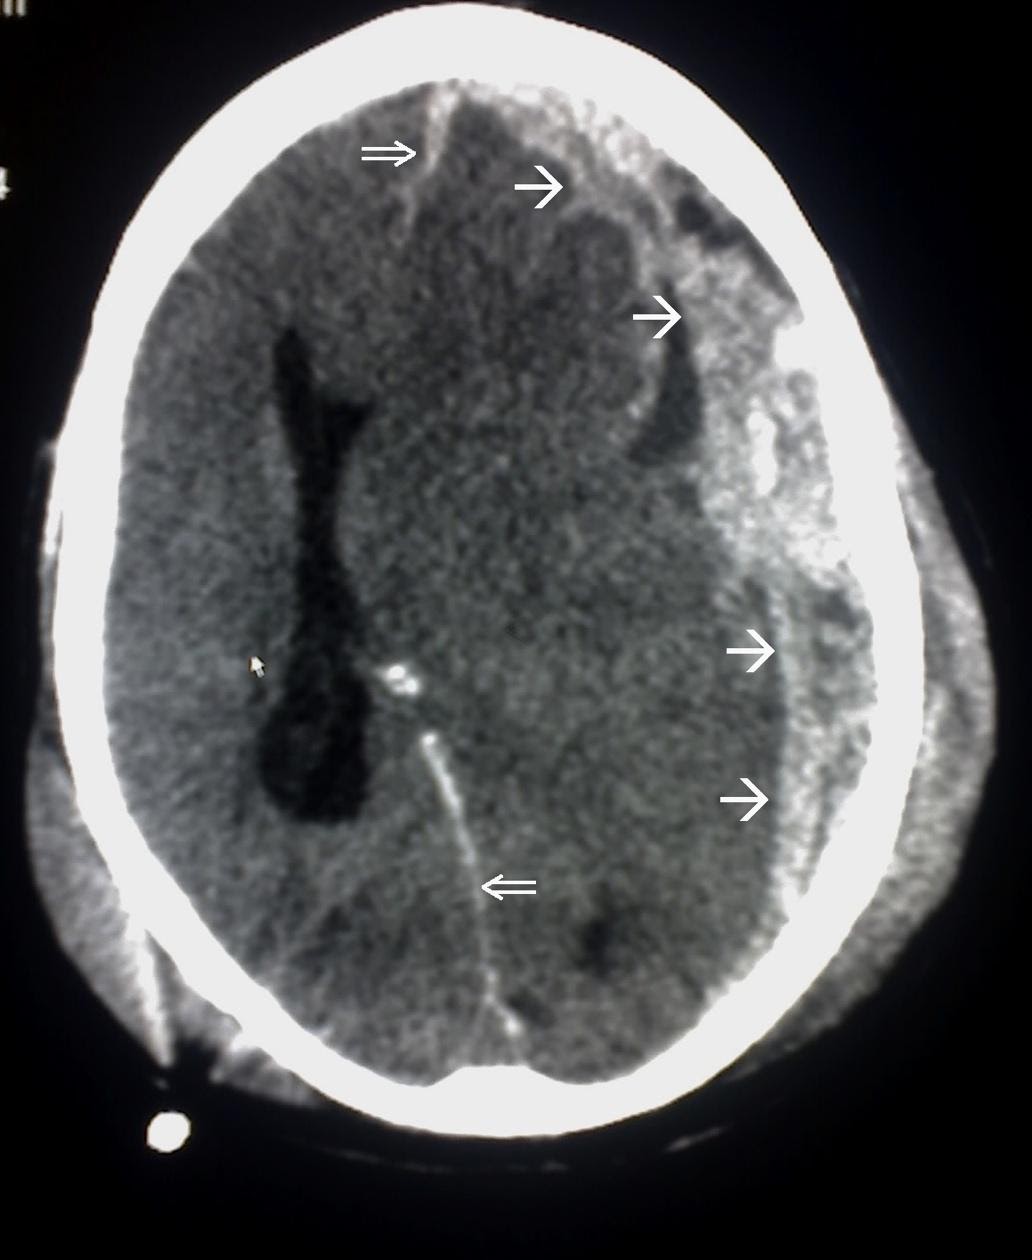

Subdural Hematoma

Subdural hematomas appear convex, or crescent-shaped, on CT and may cross suture lines. An example of a CT scan of a subdural hematoma is shown in Image 2.

Image 2. Subdural Hematoma on CT scan. Border of the SDH is denoted by the white arrows ( added for emphasis) Image courtesy of : https://commons.wikimedia.org/wiki/File:Trauma_subdural_arrows.jpg This file is licensed under the Creative Commons Attribution-Share Alike 3.0 Unported license.